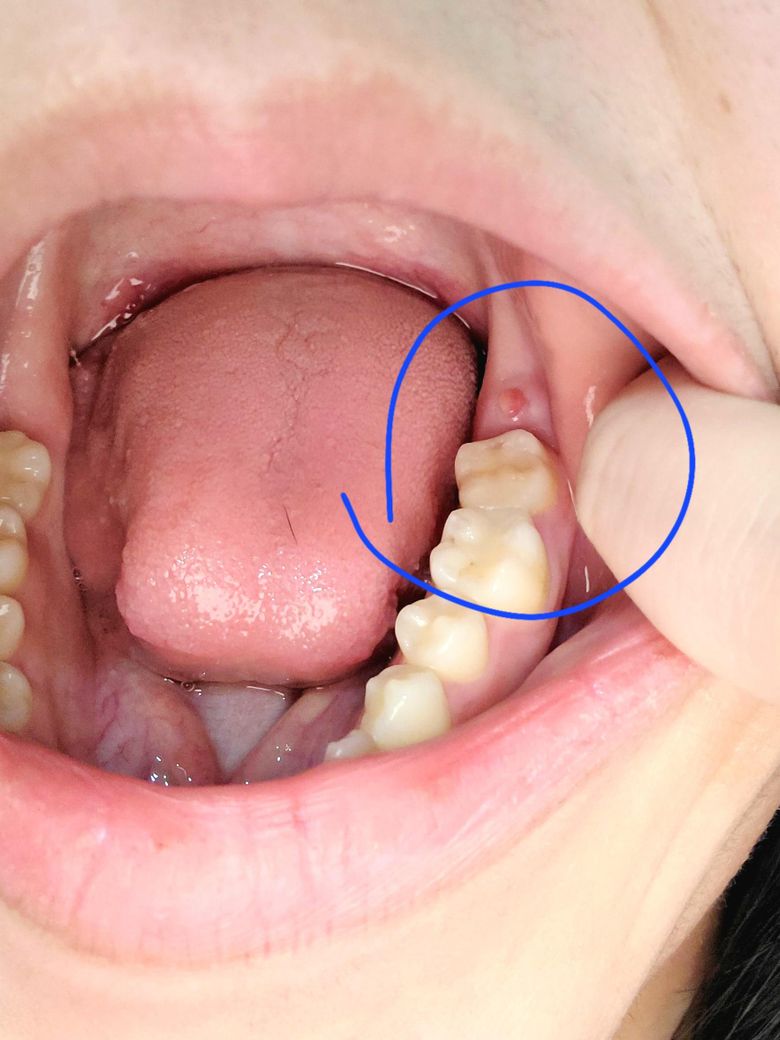

이거 사랑니 나오는 건가요?????

동그라미 부분이 약간 불편해서 봤는데

이거 사랑니 나오는건가요?

정확한건 엑스레이를 찍어봐야 알겟지만, 갑자기 저런경우라면 사랑니 떄문에 그럴가능성이 높습니다.

사랑니가 자라나는 것으로 보이며 염증에 의해 부은 것으로 보입니다. 치과가서 확인해보시는 게 좋겠습니다.

네 위치상 사랑니일 것 같습니다. 사랑니는 10대후반부터 20대 초반까지 맹출력이 남아있습니다. 부분매복된 사랑니는 잇몸 염증을 유발하기도 합니다. 치과가서 엑스레이찍어보고 체크해보세요.

사랑니가 나오려고 하는 것으로 보이며 치과에 방문하여 상태를 확인하고 발치여부를 결정하길 권합니다. 방향이 비뚤어진 경우 방치에 앞의어금니를 상하게 할수 있습니다.